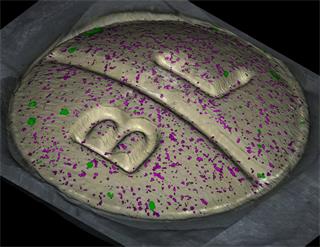

Rapidly generate images of your formulations with StreamLine™. This uses line focus illumination, allowing you to use higher laser powers without risk of sample damage, thereby reducing experiment times.

With the RA802 pharmaceutical analyser you can achieve imaging speeds of over 1500 spectra/s. It takes less than 2 minutes, from placing a standard tablet in the system, to generate a full, high resolution Raman image.

Generate images of formulations

Ensure your chemical images are representative; use Renishaw's StreamLine. You can change resolution to suit your domain size and, because Renishaw's WiRE software can cope with massive data files, you can analyse over the entire sample surface. Powerful Renishaw features, such as Slalom (to ensure the whole surface is sampled) and HD imaging (to get crisp clear images), provide all the options you need, whatever your formulation.